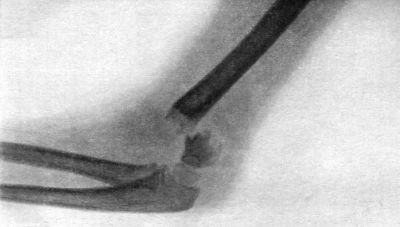

90 38.Radiogram of Incomplete Backward Dislocation of Elbow

A bone may be broken at several places, constituting a multiple fracture (Fig. 1).